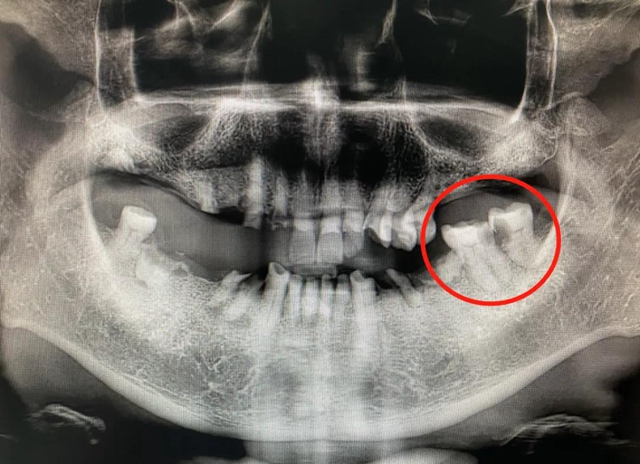

随后,罗艳燕仔细查看了王老先生的口腔全景片,发现问题并非如此简单。“王老先生左上磨牙缺失,双尖牙过度磨损,左下磨牙残根存在,左下最后两颗磨牙邻面龋坏及髓,是37、38牙在作怪,应当拔除左下后牙。”罗艳燕介绍。

王老先生及家属露出疑惑面容,为啥上牙疼痛要拔除下牙,而且要拔的是看起来还好的那两颗牙?罗艳燕随即做好了相关解释解除了他们的疑惑。